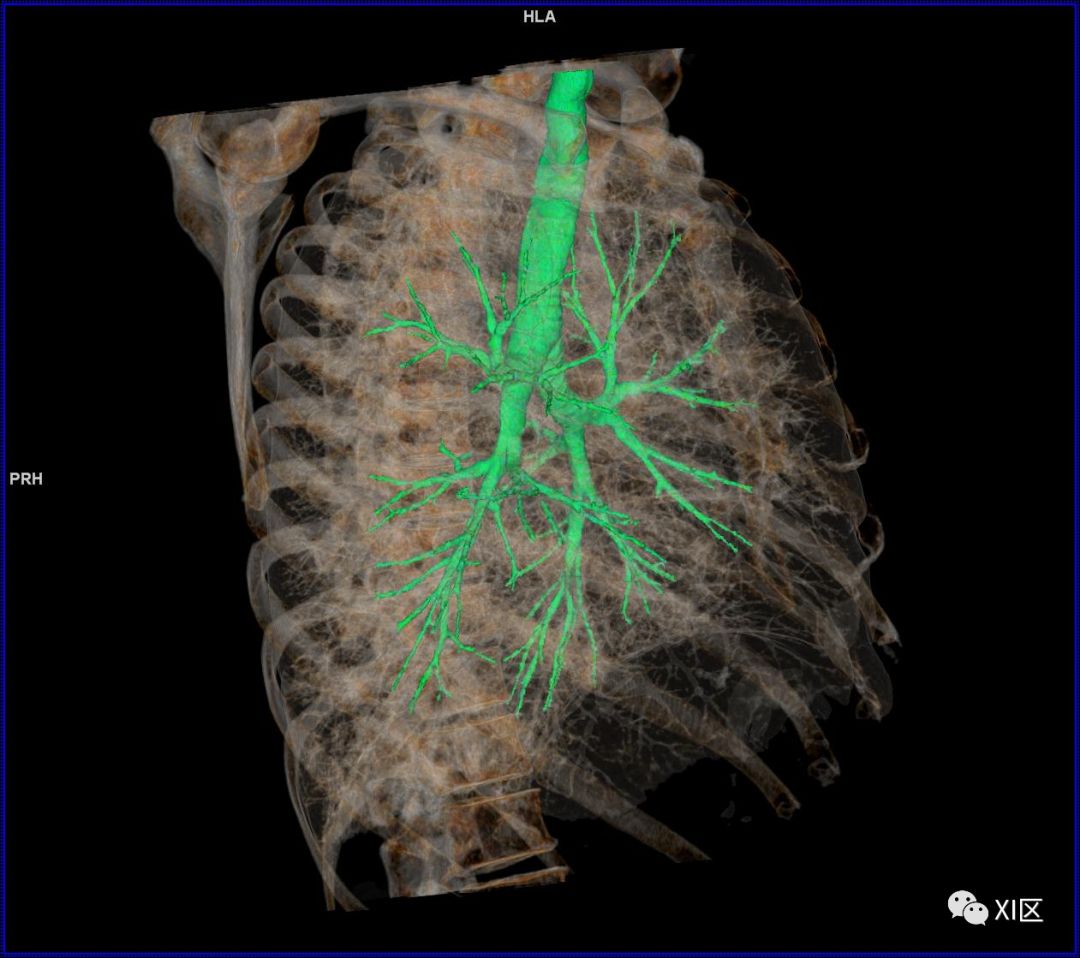

前后位,双侧位,后前位显示气道肺与胸部骨骼的关系

气管树与左右肺的关系

气管树与胸部其他结构的关系 医学百科网 | YxBaike.Com